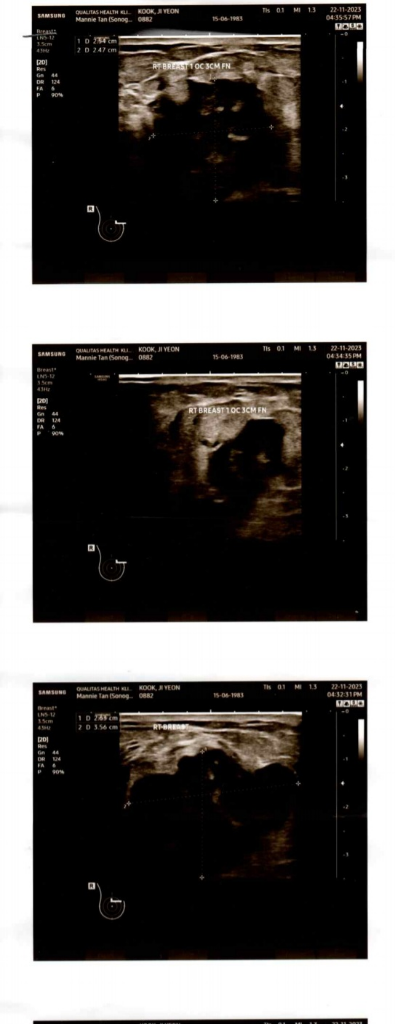

유방암 초음파 사진은 이런 모양일까요?

약 4-5개월전에 가슴에서 작은 몽우리가 만져졌는데 딱히 증상이 없어서 그냥 지나치다가 몇일전부터 약간 당기는 느낌의 통증이 있어서 가까운 클리닉에 방문했는데 그곳에서 초음파를 찍어보니 이런 모양인데 암인지는 확신할 수 없지만 모양이 별로 좋지 않다고 큰병원을 가보라고 하는데 지금 당장 큰병원 갈 형편이 아니라서요... 혹시 단순 염증 일수도 있을까요? 피검사 결과 CA 15.3에서 5.4 U/ml이 나왔거든요 제가 내년 2월에 귀국예정이라 그때 한국에서 병원에 가고 싶은데 그때까지 기다려도 될까요?

• 1번 째 사진

• 2번 째 사진

유방의 덩이가 큰 편이고, 경계가 울퉁불퉁하며 침윤하는 듯한 모양새를 보이고 있어 조직검사가 필요한 병변이라 보입니다. 4-5개월 전부터 불편함을 느끼기 시작했으니 되도록 빨리 검사해보시는게 안전하겠습니다.